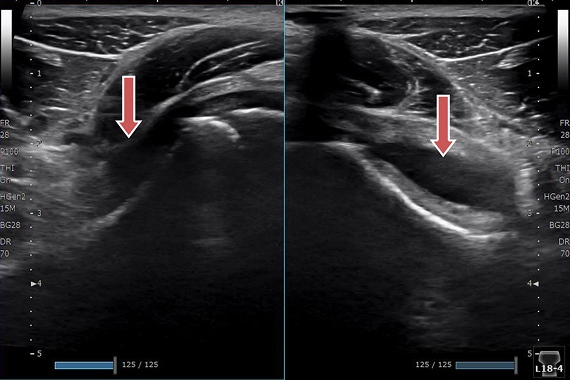

野球肘

左右を比較すると離断性骨軟骨炎の所見がはっきりわかります。